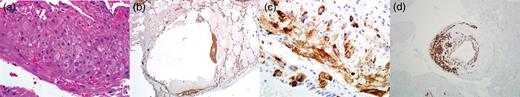

Ten days after commencing ECMO and at 24 weeks gestational age, the patient developed preeclampsia and HELLP syndrome. The maternal fetal medicine team performed an urgent cesarean section, and a viable female neonate was delivered. Simultaneously, a right-sided wedge biopsy of the lung was performed, and based on histologic findings, the diagnosis of LAM was confirmed (Fig. 2a–d). On ECMO Day 14 and Post-operative Day 3 from cesarean delivery, the patient was successfully decannulated from the ECMO circuit. She was extubated to high-flow nasal cannula (HFNC) 2 days later. Over the course of 2 weeks, she was successfully weaned to room air. The neonate required significant ventilatory and nutritional support but was eventually discharged home without neurologic disability.

Histologic images from lung biopsy demonstrating perivascular leukocytic infiltrate (H&E 400×) (a), staining for smooth muscle actin (SMA 40×) (b), Hmb-45 (400×) (c) and desmin (100×) (d).

LAM is a rare and progressive systemic disease that involves smooth muscle infiltration of the lung, culminating in cystic change of lung parenchyma [3]. The diagnosis of LAM during pregnancy is associated with significantly worse maternal outcomes including an increased incidence of premature delivery [4]. Histologic studies of LAM have demonstrated variable expression of estrogen/progesterone receptors, suggesting a hormonal role in the pathogenesis of LAM [5]. VEGF-D is a serologic marker for LAM, and levels >800 pg/ml have been shown to have 100% specificity [6]. Tissue staining for smooth muscle actin, desmin and HMB-45 is diagnostic for LAM [3]. In a randomized controlled trial, initiation of sirolimus in patients with LAM culminated in preservation of FEV1 and FVC at 1 year compared with placebo; however, this treatment effect was not sustained after cessation of therapy [7]. Limited evidence exists regarding the safety of mTOR inhibitors, specifically sirolimus, during pregnancy.